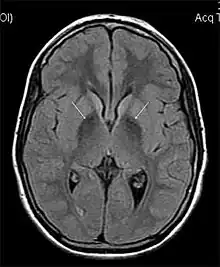

| MRI hypointensity (white arrows) in the globus pallidi that indicates the presence of iron deficiencies which would be seen in a diagnosis of Aceruloplasminemia | |

Diagnosis of this disorder depends on blood tests demonstrating the absence of serum ceruloplasmin, combined with low serum copper concentration, low serum iron concentration, high serum ferritin concentration, or increased hepatic iron concentration. MRI scans can also confirm a diagnosis; abnormal low intensities can indicate iron accumulation in the brain.[5]